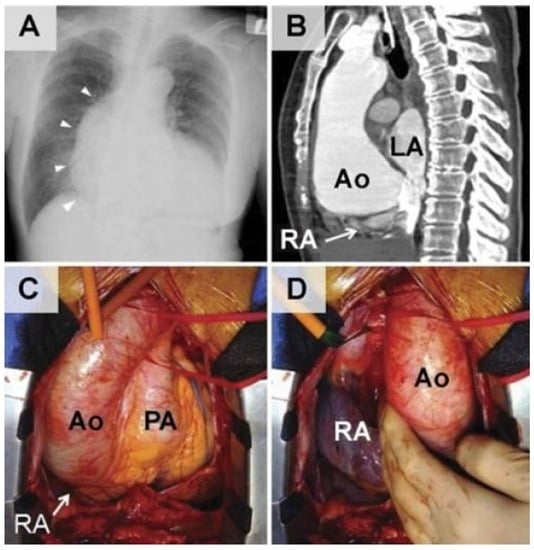

- Nakahira, A.; Matsumura, Y.; Tatsumi, H.; Sasaki, Y.; Hirai, H.; Hanatani, A.; Muro, T.; Yoshiyama, M.; Suehiro, S. Platypnea-orthodeoxia diagnosed by sitting transesophageal echocardiography. Ann. Thorac. Surg. 2010, 89, 1284–1286. [Google Scholar] [CrossRef] [PubMed]